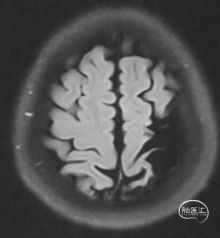

病人乙的影像资料:

T2 Flair:右侧内分水岭腔梗灶

弥散:阴性